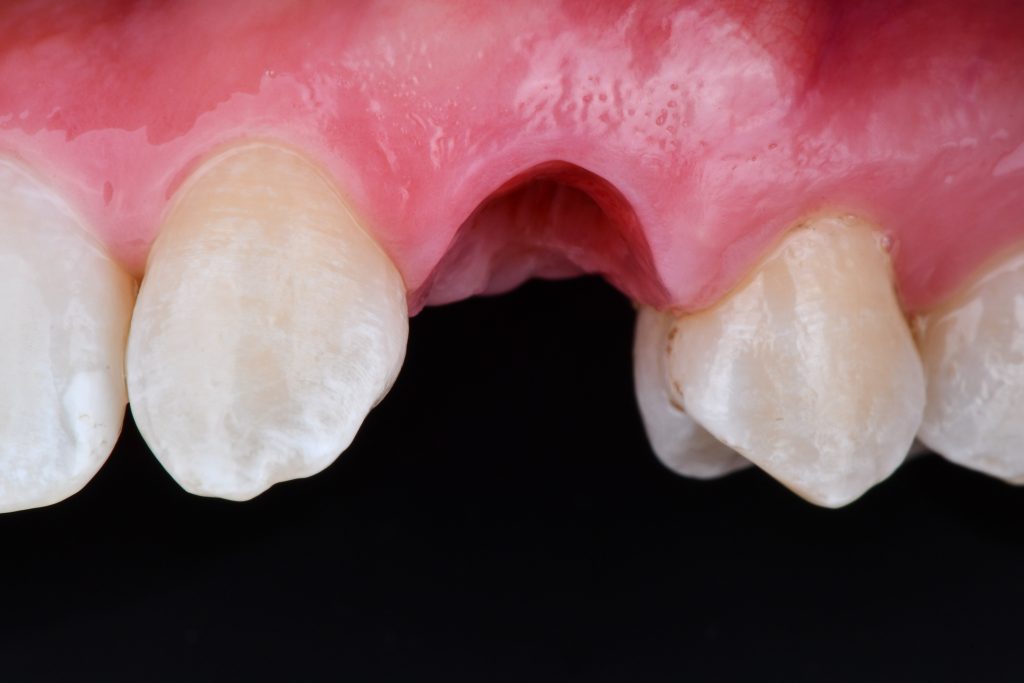

the tooth 23 is already in contact with the upper left incisor

the root of the tooth 23 was moved out of the bone envelope however the patient denied to continue in ortho Tx

the tooth 23 still in shape of a cuspid